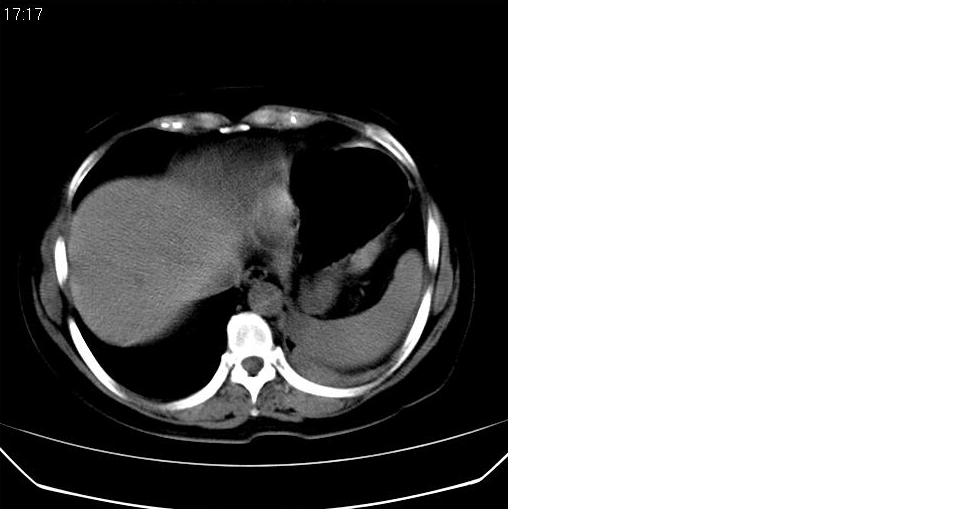

女 59岁,胸背疼,不咳嗽,不咳痰,不发热。

1)考虑左肺下叶背段周围型肺癌并左肺下叶及左侧胸膜转移。2)左侧胸腔积液。3)左冠状动脉钙化。

支持楼上,左侧膈肌抬高,考虑膈疝或膈麻癖可能。

1)考虑左肺下叶背段周围型肺癌并左肺下叶及左侧胸膜转移。2)左侧胸腔积液。

1)考虑左肺下叶背段周围型肺癌(腺癌可能性大)并左肺下叶及左侧胸膜转移。2)左侧胸腔积液。3)左冠状动脉钙化。